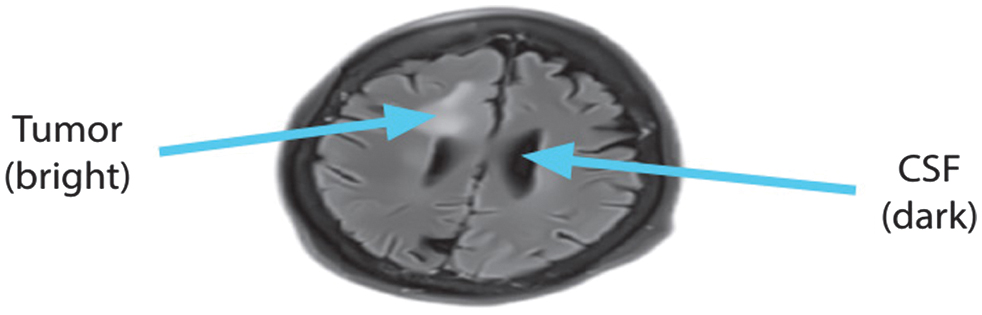

While the FLAIR MRI picture is strikingly similar to T2-weighted imaging in terms of brain tissue intensities, the main difference is that CSF appears dark instead of brilliant. The secret to its success is a combination of extended echo (TE) and repetition (TR) periods that selectively muffle water signals. When viewed by FLAIR imaging, CSF is dark and gray matter is brighter than white matter. The evaluation of brain illnesses such as infarction, hemorrhage, and head traumas might greatly benefit from FLAIR sequences due to this specific feature. Reducing CSF fluid production is an additional advantage of FLAIR imaging. As shown in Fig. 1, this is an example of a FLAIR image’s axial view.